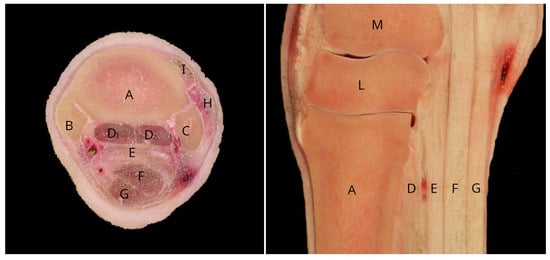

- Nagy, A.; Dyson, S. Magnetic Resonance Anatomy of the Proximal Metacarpal Region of the Horse Described from Images Acquired from Low- and High-Field Magnets. Vet. Radiol. Ultrasound 2009, 50, 595–605. [Google Scholar] [CrossRef] [PubMed]

- Bischofberger, A.; Konar, M.; Ohlerth, S.; Geyer, H.; Lang, J.; Ueltschi, G.; Lischer, C. Magnetic Resonance Imaging, Ultrasonography and Histology of the Suspensory Ligament Origin: A Comparative Study of Normal Anatomy of Warmblood Horses. Equine Vet. J. 2006, 38, 508–516. [Google Scholar] [CrossRef] [PubMed]